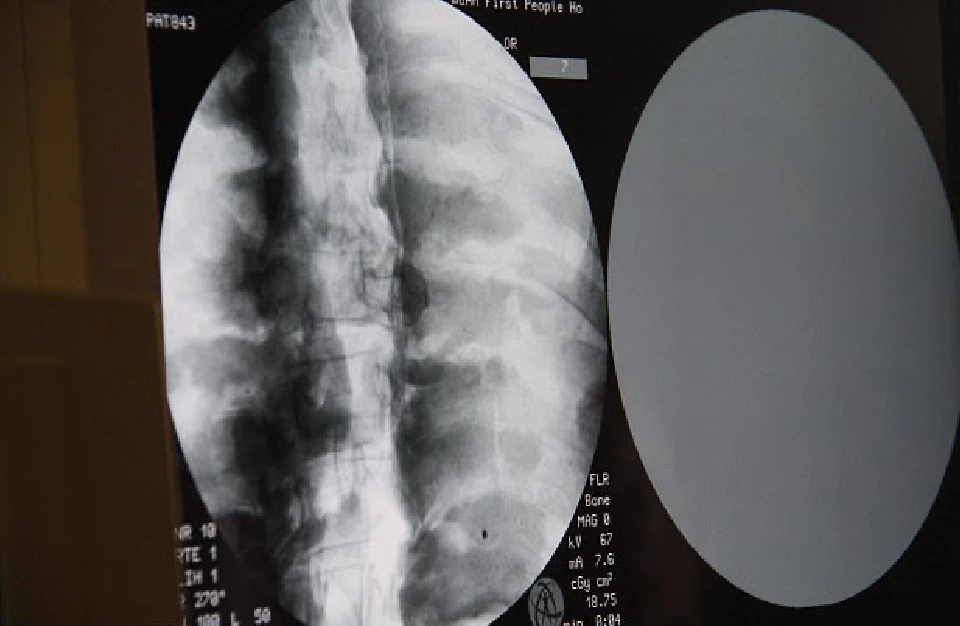

Bước ngoặt thực sự diễn ra vào ngày 8 tháng 7 năm 2017, khi các nhà khoa học phối hợp cùng bệnh viện địa phương quyết định tiến hành chụp CT (cắt lớp vi tính) ngay tại khuôn viên nhà chùa dưới sự chứng kiến của giới truyền thông và hàng nghìn người dân hiếu kỳ. Khi những hình ảnh quét đầu tiên xuất hiện trên màn hình máy tính, cả khán phòng đã rơi vào trạng thái im lặng đến nghẹt thở vì kinh ngạc.

Dưới lớp mạ vàng dày, hình ảnh quét CT hiện rõ mồn một cấu trúc của một cơ thể người hoàn chỉnh. Bác sĩ Wu Yongqing, người trực tiếp điều hành buổi kiểm tra, đã phải thốt lên rằng đây là một kỳ tích chưa từng thấy trong y học và khảo cổ. Kết quả cho thấy toàn bộ hệ thống xương của nhà sư Ci Xian vẫn chắc khỏe và rõ nét như của một người đang sống.

Từ những chi tiết nhỏ nhất như xương hàm trên, hàm răng đều tăm tắp cho đến xương sườn, xương sống và các khớp xương đều giữ được vị trí nguyên vẹn, không hề có dấu hiệu của sự phân hủy hay mục nát do thời gian. Đáng kinh ngạc hơn cả chính là bộ não của ngài; thay vì bị teo hoàn toàn theo quy luật tự nhiên, hình ảnh quét cho thấy khối óc vẫn còn giữ được hình dáng cấu trúc tương đối hoàn chỉnh, nằm bình yên bên trong hộp sọ.